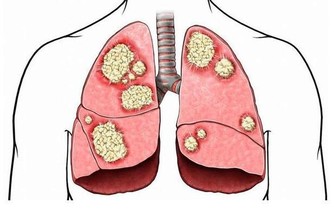

肺癌幫數據分析各類型肺癌發病特點及存活期限

1、小細胞肺癌:癌細胞生長快,轉移快

據肺癌幫APP病例庫統計,小細胞肺癌約佔10%。小細胞肺癌,其癌細胞生長的速度快,轉移也迅速,且容易有抗藥性,大多為吸煙所引起,也與環境或基因有關。

小細胞肺癌基本都活不過兩年。在治療方面,國外有人嘗試用手術,但是基本以放化療為主。

2、肺腺癌:最常見,多為女性

肺腺癌約佔50%,以女性為主。肺腺癌為最常見的肺癌,也是不吸煙者(多數為女性的45歲以下)常見的類型,容易遠端轉移是其特徵。治療的原則得根據期別,通常一、二期可經由評估後進行手術,之後再做化療等。

關於肺癌手術目前的效果,專家表示,一期a(腫瘤小於3公分,無轉移),開刀治好的機率可高7、8成,發現率則為20%左右;一期b(腫瘤大於3公分,無轉移)復發率為一半;第二、三期當然就更高。第三、四期不適合手術者,通常會建議採用化療控制腫瘤病情並抑制癌細胞生長。

3、鱗狀上皮細胞癌:早期多為局部向外延伸的轉移

鱗狀上皮細胞癌,約佔30%,吸煙男士居多。常常發生在男性吸煙者,早期多為局部向外延伸的轉移,後期則經由血路擴散。

關於治療方面,專家分析:鱗狀上皮細胞癌目前並無有效的靶向藥,但對放射性治療的效果肺腺癌好。早期的鱗狀上皮細胞癌開刀即可醫治;當然,若已經不能開刀,也可放化療雙管齊下,希望能有效控制腫瘤。

4、大細胞肺癌:生長速度快,預後不佳

患者人數約佔肺癌的5%,生長速度較快,會迅速經由血路及淋巴擴散,預後不佳。